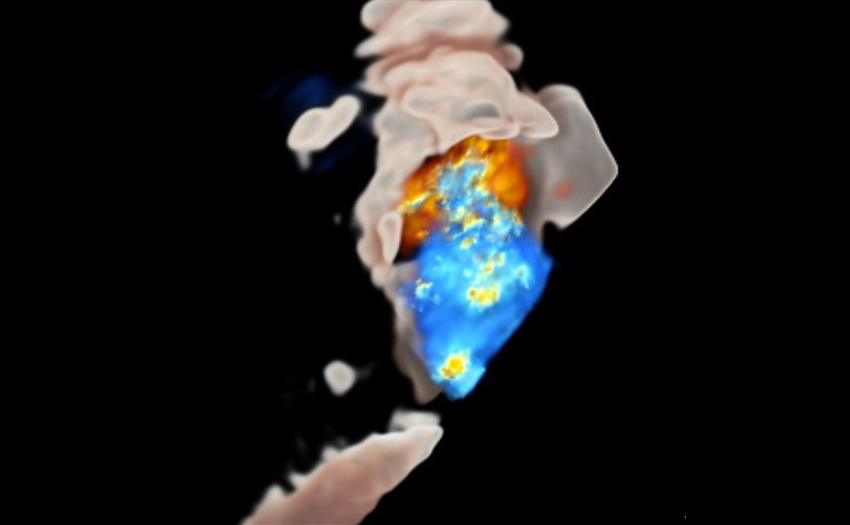

- Advanced Echocardiography: State of the art training on 3D TTE/TEE, Strain, Structural/Interventional Echocardiography. Participation in the latest clinical trials and latest structural interventions. Unparalleled interventional echo experience: (600 TAVR per year, 100 mitral interventions per year, 300 left atrial appendage occlusions per year, 50 tricuspid interventions per year).

- Cardiac CT: Full Cardiac and Cardiovascular CT training on 256 slice GE Revolution scanner. Including Coronary CTA, Vascular CTA and preoperative structural CT imaging for transcatheter intervention planning.

- Cardiac MRI: Additional training possible in Cardiac MRI in collaboration with both the Cardiology and Radiology departments.